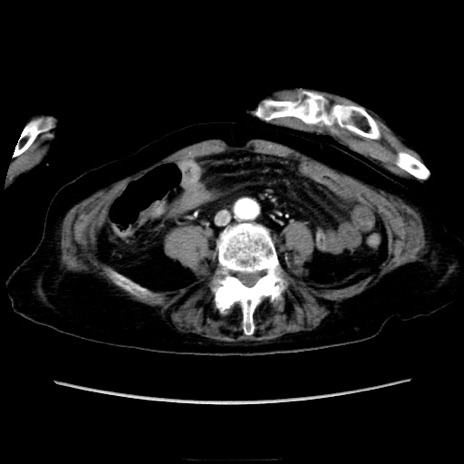

症例40(横断像)

【症例】90歳代女性

【主訴】腹痛・嘔吐

【現病歴】 食欲低下、嘔吐があり昨日他院受診。肺炎と診断され入院となる。入院後より腹部全体に圧痛あり。胃管留置され経過みていたが、症状持続するため、

当院転院となる。

【身体所見】腹部:中央に激痛あり、圧痛あり、反跳痛不明

【データ】WBC 17100、CRP 18.82

他院CT